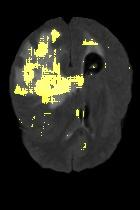

Current unsupervised anomaly localization approaches rely on generative models to learn the distribution of normal images, which is later used to identify potential anomalous regions derived from errors on the reconstructed images. However, a main limitation of nearly all prior literature is the need of employing anomalous images to set a class-specific threshold to locate the anomalies. This limits their usability in realistic scenarios, where only normal data is typically accessible. Despite this major drawback, only a handful of works have addressed this limitation, by integrating supervision on attention maps during training. In this work, we propose a novel formulation that does not require accessing images with abnormalities to define the threshold. Furthermore, and in contrast to very recent work, the proposed constraint is formulated in a more principled manner, leveraging well-known knowledge in constrained optimization. In particular, the equality constraint on the attention maps in prior work is replaced by an inequality constraint, which allows more flexibility. In addition, to address the limitations of penalty-based functions we employ an extension of the popular log-barrier methods to handle the constraint. Comprehensive experiments on the popular BRATS'19 dataset demonstrate that the proposed approach substantially outperforms relevant literature, establishing new state-of-the-art results for unsupervised lesion segmentation.